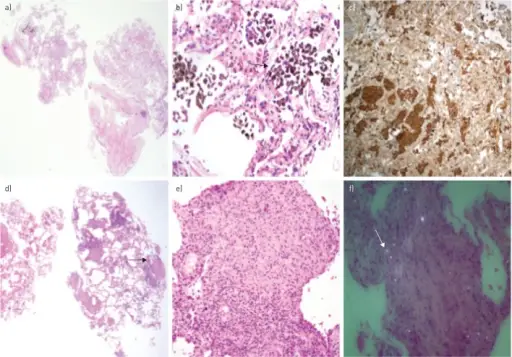

Bronchopneumonia

Bronchopneumonia is characterized by patchy, sporadic consolidation, concentrated on the bronchioles.

Bronchopneumonia is frequently bilateral and multifocal.

Bronchopneumonia is caused by different bacterial species.

Lobar Pneumonia

Lobar pneumonia is characterized by the consolidation of a whole lung lobe.

Interstitial Pneumonia

Interstitial pneumonia is also known as atypical pneumonia.

Diffuse interstitial infiltrates are the defining features of interstitial pneumonia.